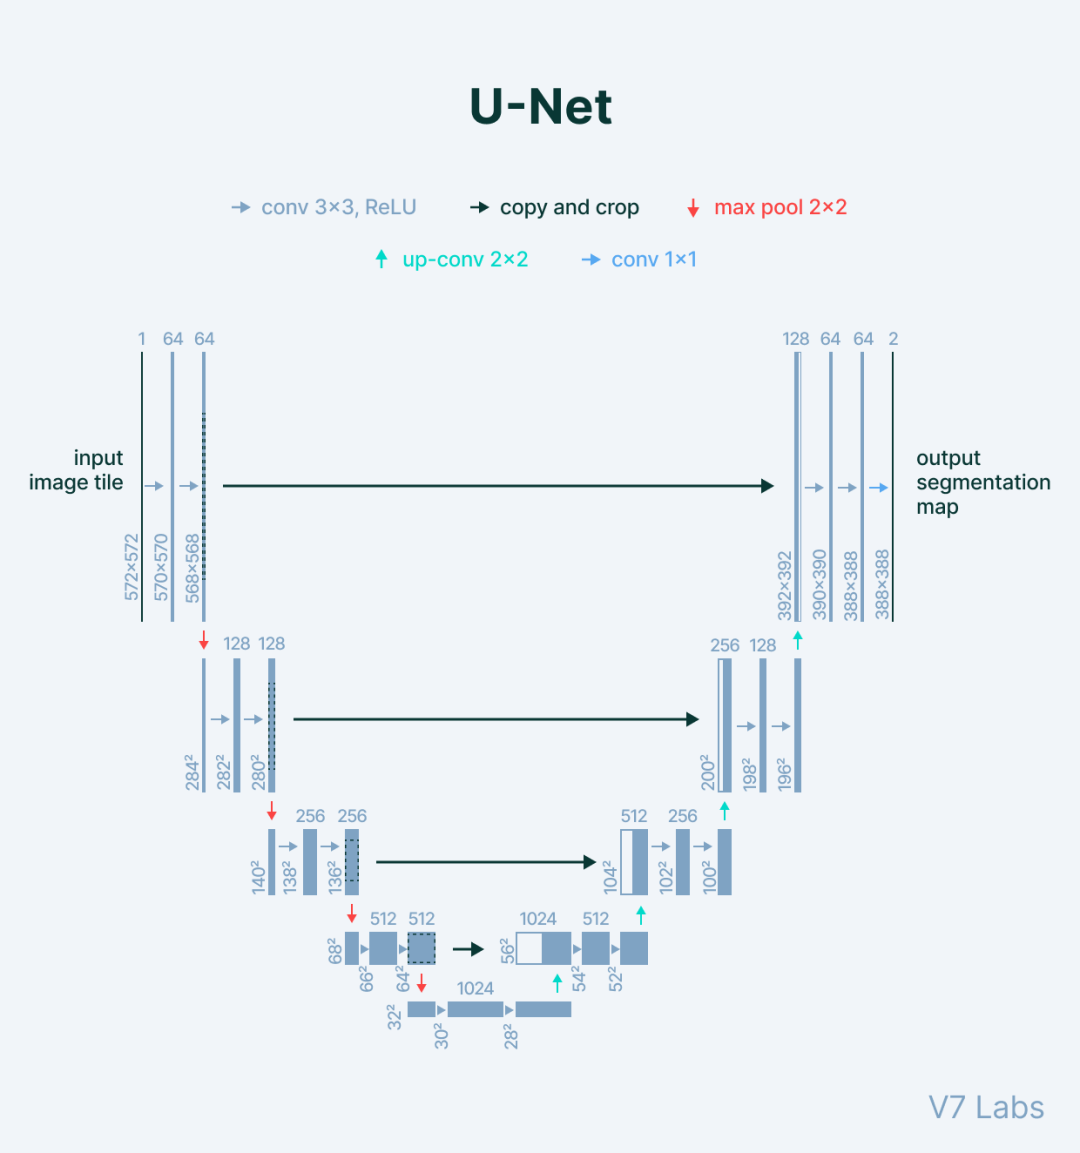

U-Net

Paper: 《U-Net: Convolutional Networks for Biomedical Image Segmentation》

Accepted by MICCAI 2016.

文章解读:https://www.zhihu.com/question/269914775/answer/586501606

U-Net最初是在由 MICCAI 举办的细胞分割挑战比赛中大获全胜,紧接着一路开挂,在场景解析、医学图像分割、显著性检测、遥感图像分割等领域遍地开花,逐渐成为了语义分割领域的新标杆,哪怕今天爆火的 AGI 技术 Diffusion 模型中也应用到了此网络结构。

编码器:用于将输入图像编码为多个不同级别的特征表示,通常由一堆卷积和池化组成;

解码器:用于将编码器学习到的判别性特征(lower-resolution)语义逐步投影至与原始空间分辨率一致的像素空间(higher-resolution)以进行密集预测分类,通常由上采样模块和卷积组成;

长跳跃连接:在网络中进行上采样的同时,将来自编码器网络的更高分辨率的特征图与上采样的特征图拼接(

Concat)起来,以便更好地学习后续卷积的表征【FCN中采用Add操作】。由于上采样是一种稀疏操作,因此引入早期阶段的良好先验可以更好地帮助网络定位到目标。